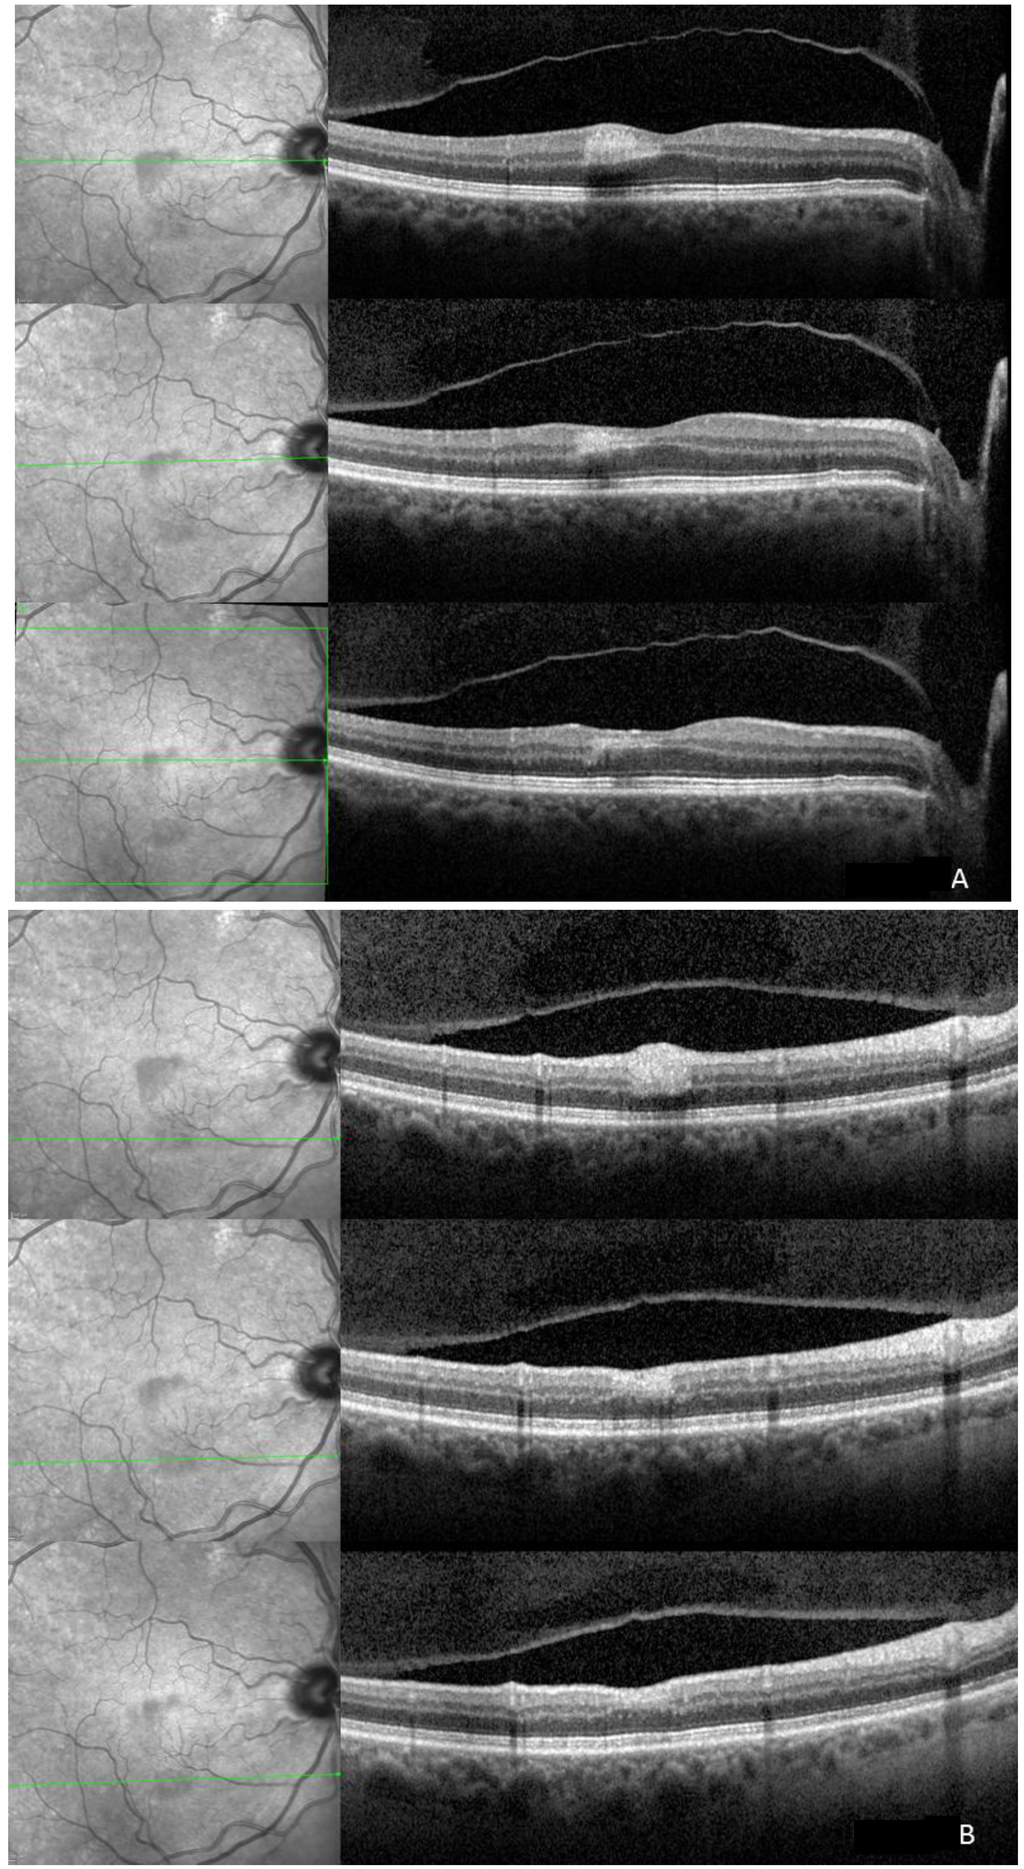

Imaging of a Cilioretinal Artery Embolisation

2. Case Report